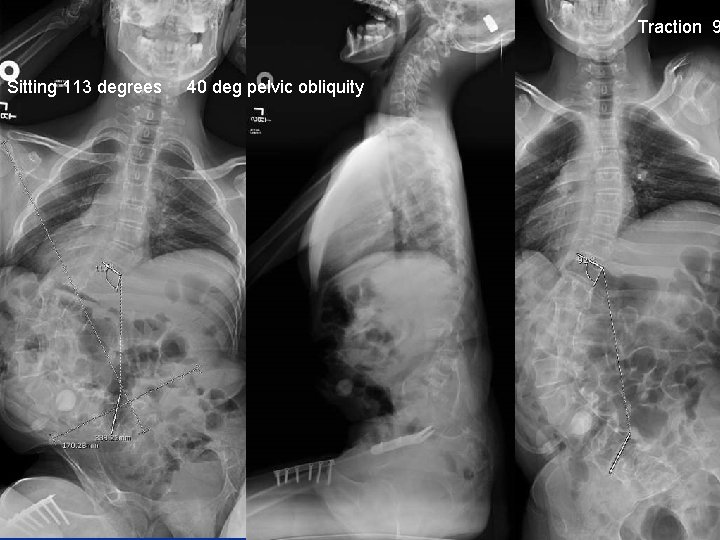

Case 1: NM Scoliosis, Marked Imbalance n n n 14 year male CP GMFCS 5 DX: 113 degree left thoracolumbar scoliosis Marked difficulty sitting and discomfort. Seizure disorder on meds Osteoporosis with history of fractures DXA: Z scores range from 10. 6 to -3. 7

Traction 9 Sitting 113 degrees 40 deg pelvic obliquity